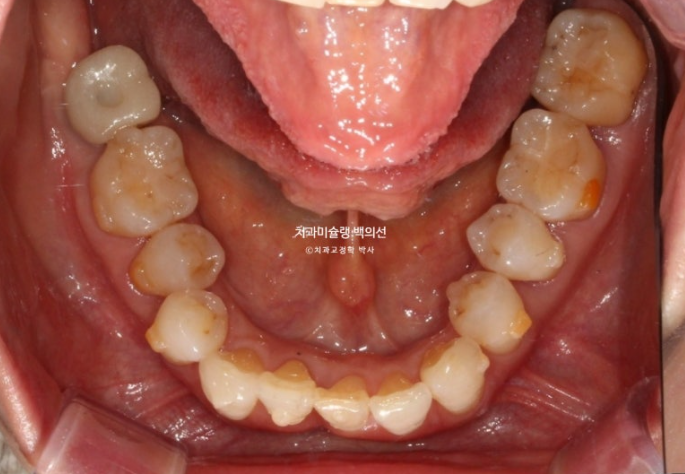

50대 발치교정 소개해드릴 압구정 인비절라인 치과 입니다.

1년 전 치아 틀어짐이 점점 심해지면서 찾아오신 50대 환자분

예전에는 입이 편하게 다물어졌었는데 치아가 틀어지고 벌어지고 내려오면서 이제는 입이 편하게 안 다물어지는 것도 불편한 상태입니다.

파란 화살표 치아는 잇몸이 검붉게 보입니다.

엑스레이상 이미 치주염이 상당히 진행이 되어 발치가 불가피한 상황이였습니다.

위 앞니는 잇몸이 꽉 잡아주지를 못해서 점점 솟아 내려오고 튀어나오면서 치아사이가 벌어졌습니다.

작은어금니도 안으로 쓰러져 있어서 이 부분은 윗니와 엇갈려 물리는 가위교합 입니다.